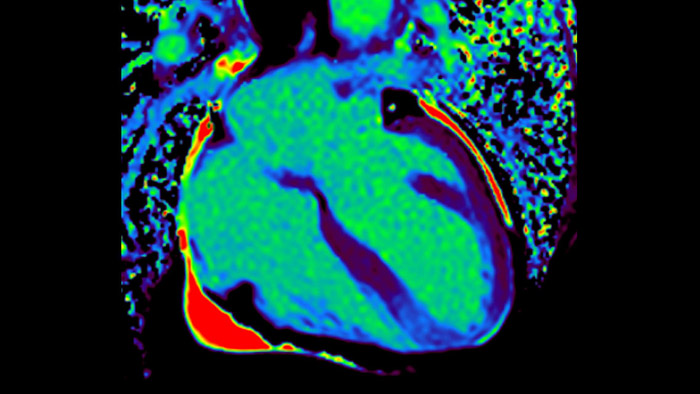

Today's diagnostics often cannot detect heart dysfunction until symptoms occur. MyoStrain utilises segmental strain to measure 48 segments of the heart and provides physicians with a unique diagnostic tool to help identify regional dysfunction before the heart as a whole is affected.

IntelliSpace Portal MR Caas5,6 Strain7 assists in patient diagnosis and monitoring by providing global strain parameters such as global longitudinal strain (GLS), global circumferential strain (GCS), and global radial strain (GRS), using short and long axis MR images, as well as describing the myocardium deformation- such as shortening, thickening, and lengthening during the cardiac cycle.